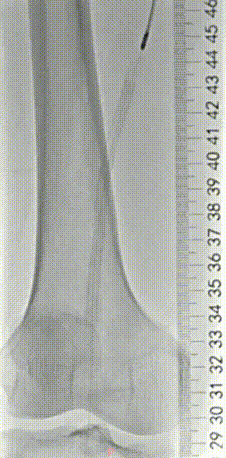

▲造影提示治疗效果良好,成功开通闭塞段。

▲Blades Up模式再次抽吸病变段,股腘动脉管腔获得满意,膝下胫后动脉、足部血流灌注同前,未见明显栓塞。

▲股浅、腘、胫后动脉经POBA+5*300 先瑞达DCB球囊扩张。

▲治疗完毕,最终造影结果,股浅动脉局部非限流性夹层,支架内、膝下流出道血流速满意。